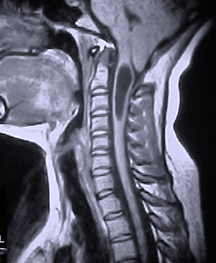

cerebellar tonsils

Images and publication that was written by Dr Johnson and his colleagues at UCLA about treatment of spinal cord injury and syrinx formation with correcting the spinal deformity